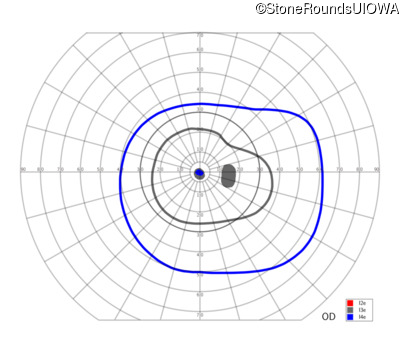

Congenital Stationary Synaptic Dysfunction (IA2g)

Congenital Stationary Synaptic Dysfunction (IA2g)

| Congenital Stationary Synaptic Dysfunction | CABP4 | Arg49Stop CGA>TGA | IVS1+1 G>T | AR |